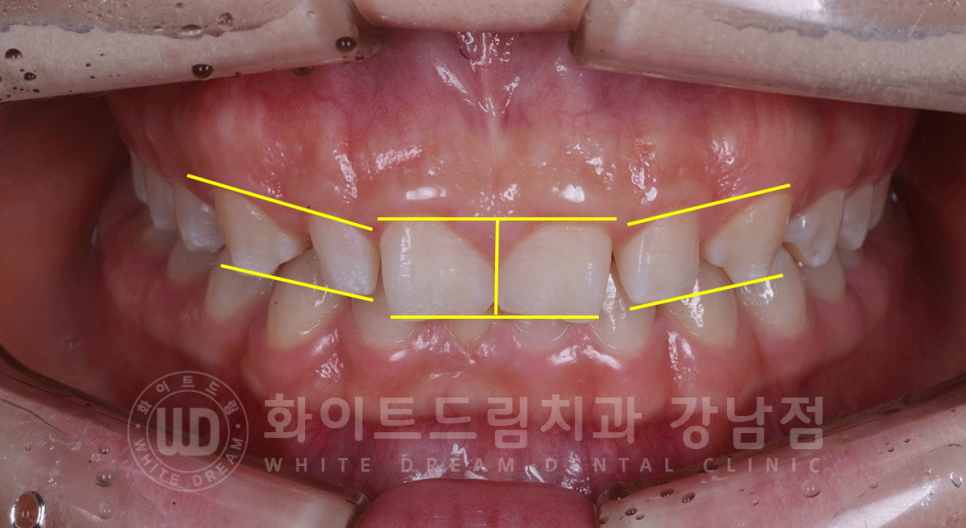

▲ 작은 치아와 거미스마일(잇몸 노출)이 동반된 CASE.

오늘 소개해 드릴 환자분은 전체적으로 치아 크기가 굉장히 작은 케이스입니다.

치아가 벌어진 원인이 2번째에 속하시는 분이시죠.

치아가 너무 짜리몽땅하고 벌어져서 스트레스예요.

어떻게 치료할 수 있나요? 교정은 하기 싫어요.

치아 자체가 작기 때문에 교정을 통해 치아를 모아주어도 심미적으로는 만족하기 어려울 수 있습니다.

게다가 환자분은 치아교정은 전혀 원하지 않으시기 때문에

잇몸성형술과 라미네이트를 통해 이러한 콤플렉스를 개선하기로 했는데요.